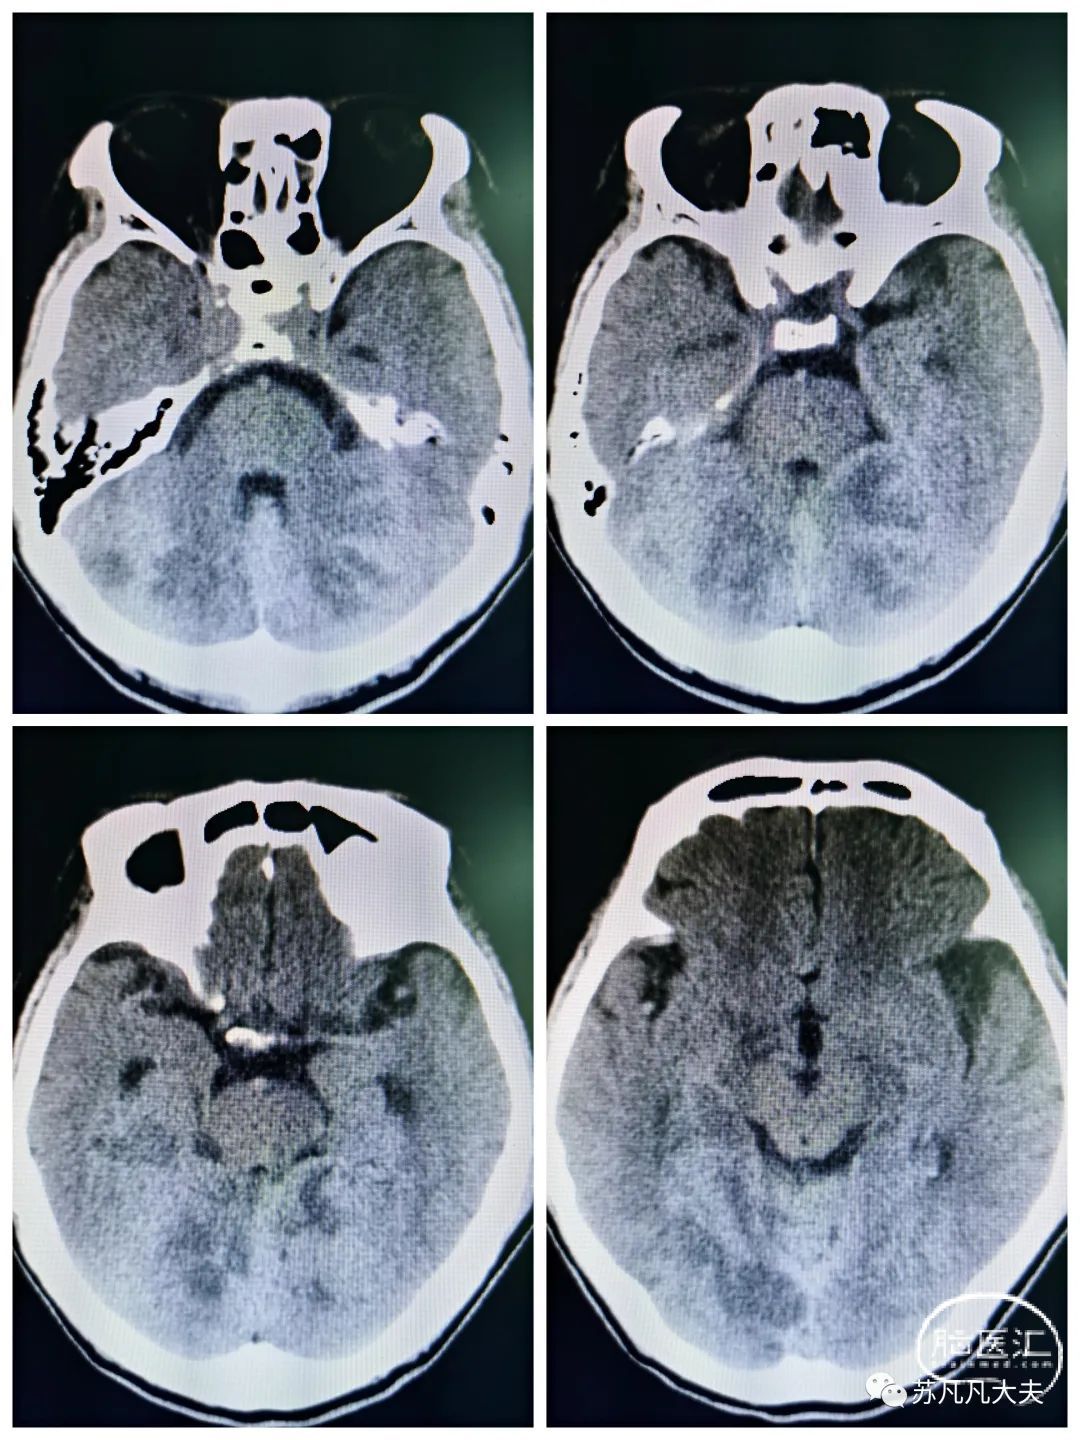

头CT可见双侧小脑梗死灶(11:33)

核磁DWI示双侧小脑,右侧颞叶,岛叶,双侧顶枕叶多发脑梗死。(19:30)

次日复查头CT见梗死灶同核磁DWI显示病灶,左侧枕叶未见新发梗死灶。